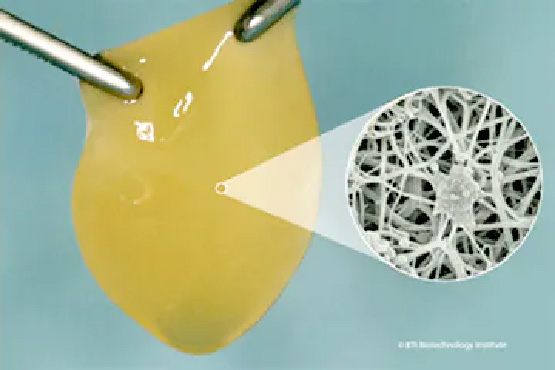

患者様自身の血液から抽出された成長因子を多く含む血漿のことで、治癒促進、組織の再生を促進する医療技術です。歯科・成形外科・美容医療など幅広く応用されています。

当院では、再生医療の中でも注目されているPRGF治療というものを行っています。患者さん自身の血液に含まれる血小板を未活性のまま取り出し患部に戻すことで、組織の再生を促す再生医療テクノロジーです。

PRGFは、「自分の血液で自分を治す」再生医療です。

ご自身の血液の中に含まれる「成長因子(グロースファクター)」を利用して、傷の治りを早めたり、骨や歯ぐきの再生を促す治療法です。

人工的な薬や他人の血液は一切使わず、ご自身の血液だけを利用する安全な方法です。